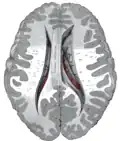

Ventricles of brain and basal ganglia. Superior view, horizontal section, deep dissection

Ventricles of brain and basal ganglia. Close-up of preceding image

Caudate nuclei along with other subcortical structures, in glass brain -